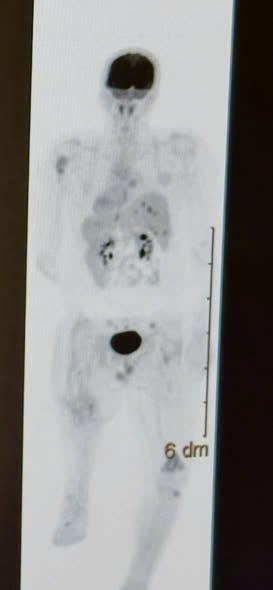

For Will and his family, the week that followed was a descent into the unknown. On December 5, a PET scan captured the state of the battlefield—a snapshot of a body under siege. At that moment, Will had not yet begun the “Cabo” chemo pill. He was standing on the precipice, facing an enemy that was moving faster than the paperwork could track.

At precisely 2:45 PM EST today, the atmosphere inside the oncologist’s office shifted from routine to surreal. The doctor opened the digital files containing the new PET scans from 1/8.

Witnesses say the room fell into a “dead silence” reminiscent of a cinematic climax. As the images flickered to life, comparing the dark shadows of December 5 to the clarity of January 8, the visual evidence was so jarring it felt like a hallucination. The “fire” in the images hadn’t just dimmed; it appeared to be retreating.

- Dec 5: Baseline PET Scan (The Calm Before the Storm).

- Jan 8, 10:00 AM: The New PET Scan is Captured.